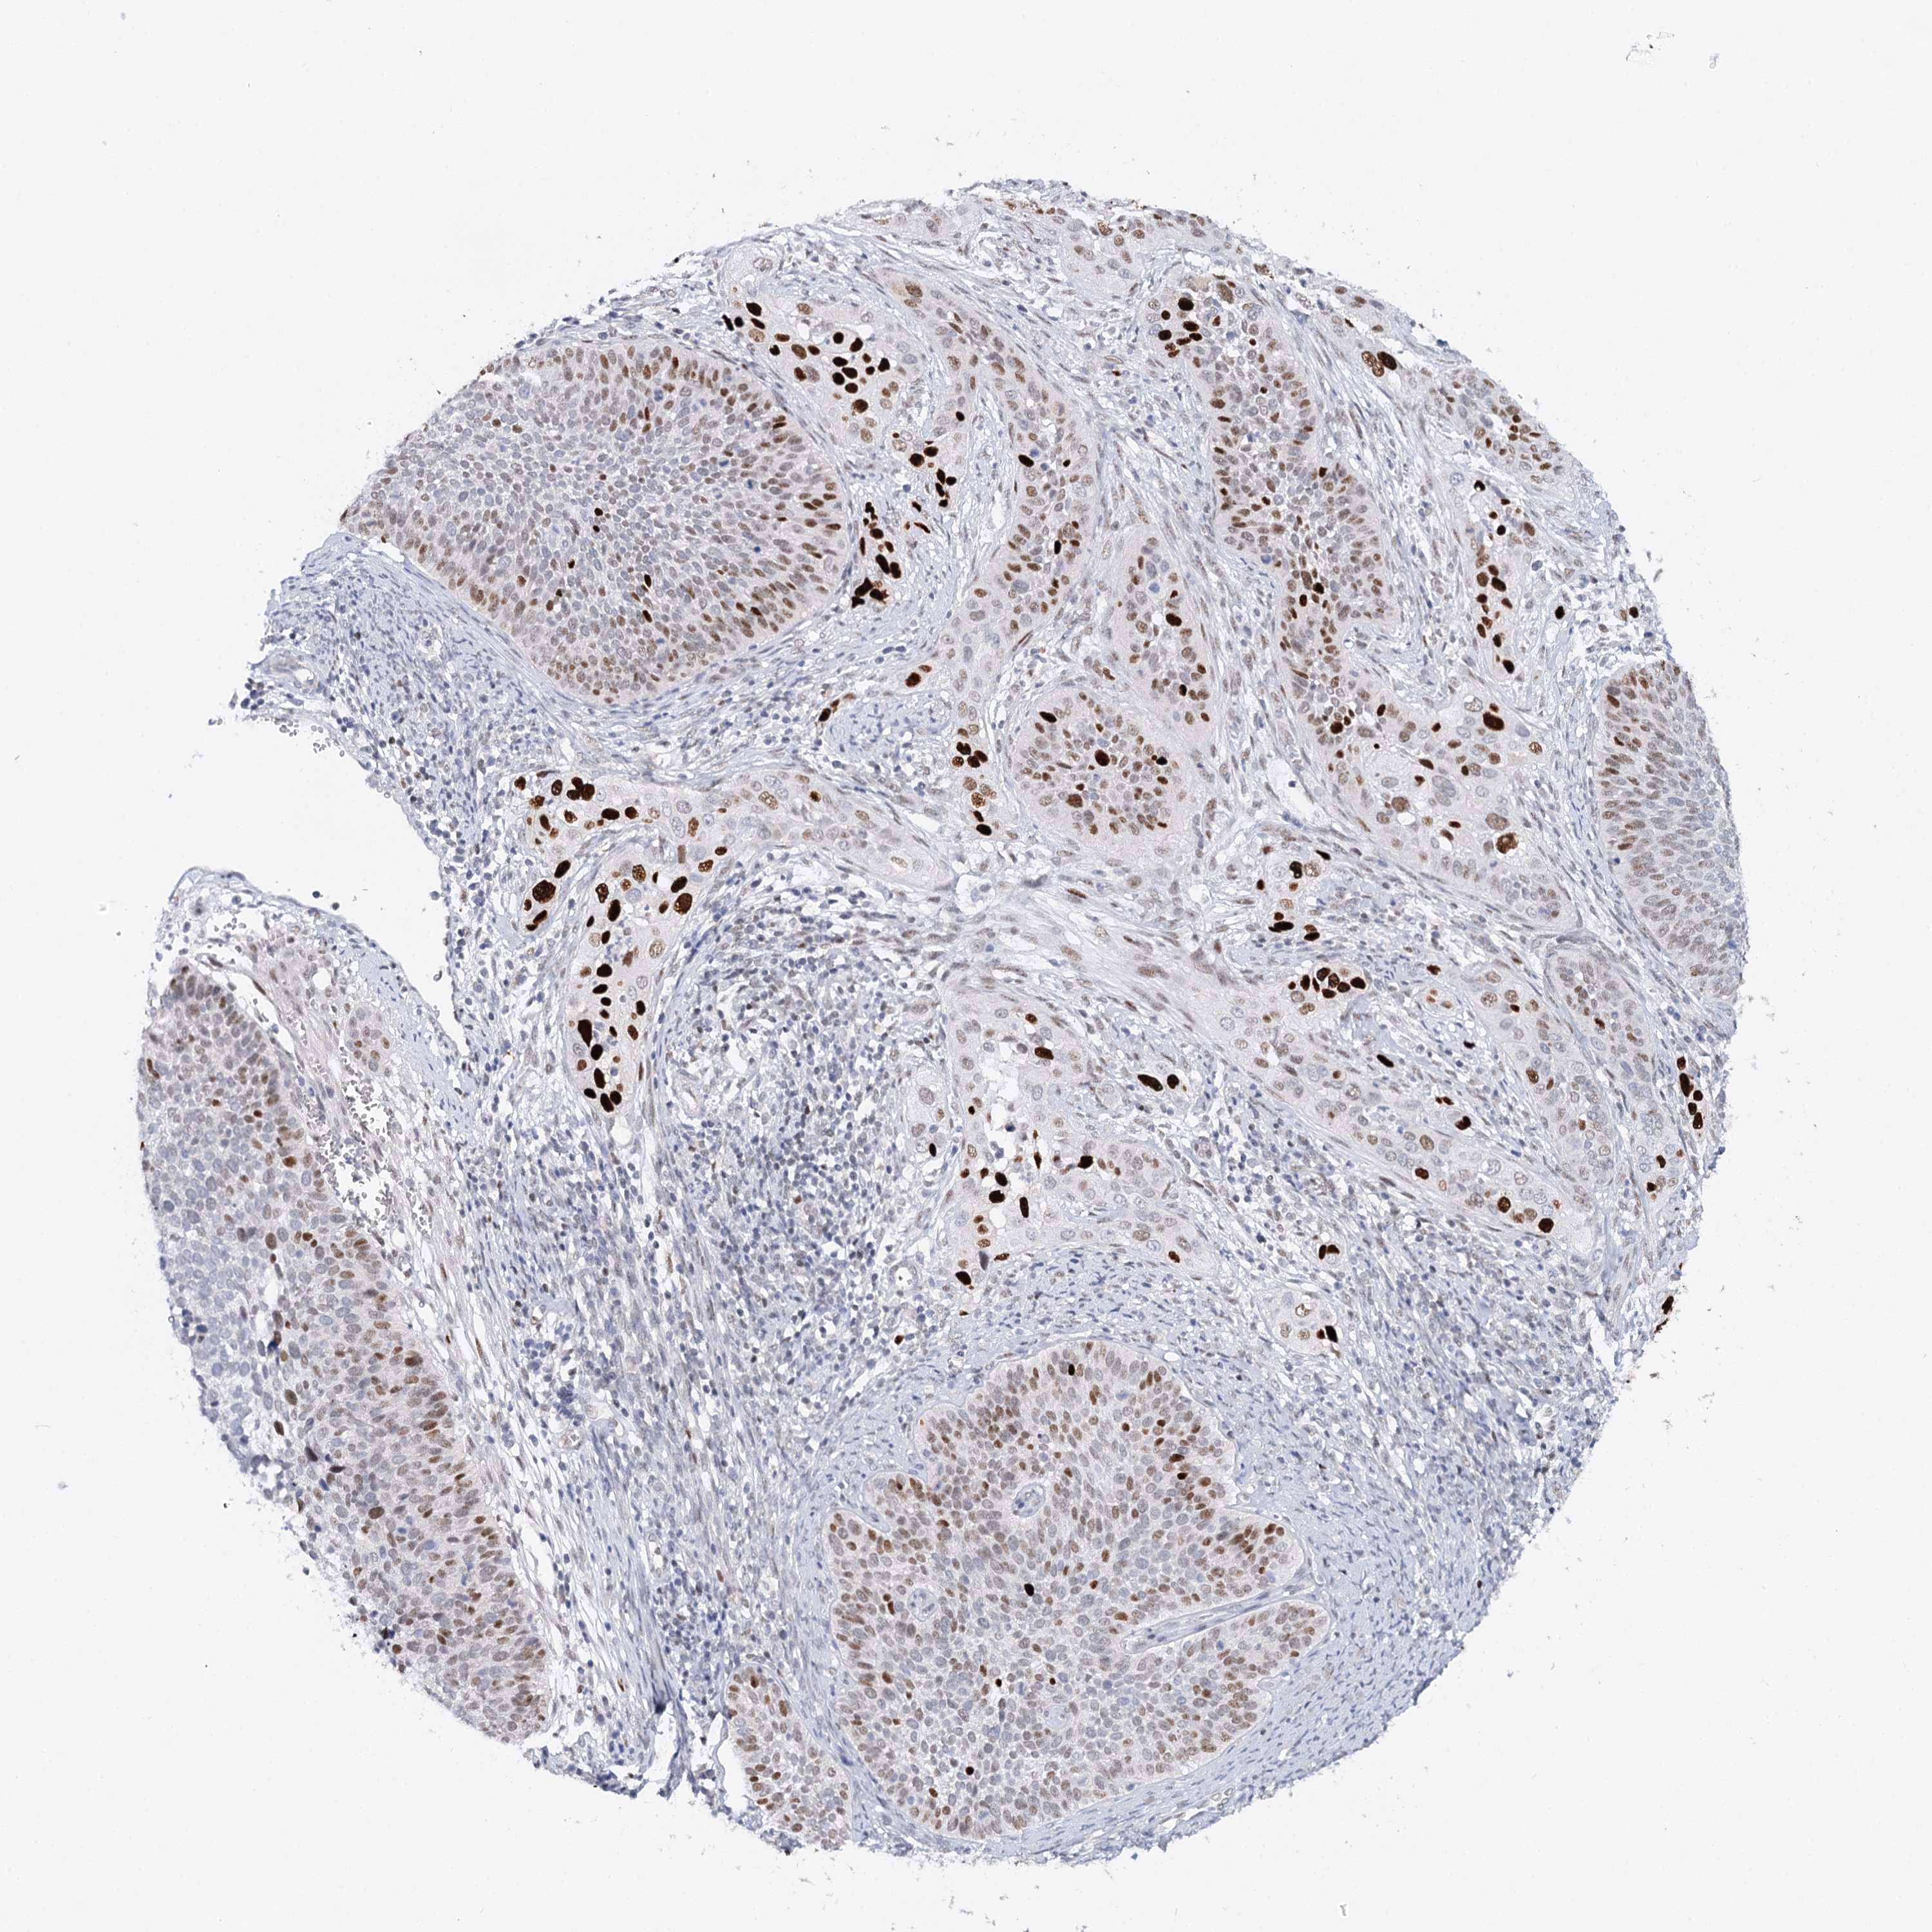

CERVICAL CANCER - Protein expressioni

A mouse-over function shows sample information and annotation data. Click on an image to view it in a full screen mode. Samples can be filtered based on level of antibody staining by selecting one or several of the following categories: high, medium, low and not detected. The assay and annotation is described here.

Note that samples used for immunohistochemistry by the Human Protein Atlas do not correspond to samples in the TCGA dataset.

Antibody stainingi

Antibody staining in the annotated cell types in the current human tissue is reported as not detected, low, medium, or high, based on conventional immunohistochemistry profiling in selected tissues. This score is based on the combination of the staining intensity and fraction of stained cells.

Each image is clickable and will lead to virtual microscopy that enables deeper exploration of all samples and also displays staining intensity scores, fraction scores and subcellular localization as well as patient and tissue information for each sample.

Antibody CAB039238

Squamous cell carcinoma, NOS